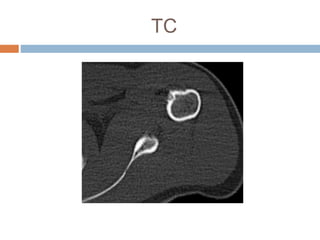

Este documento presenta el caso de un hombre de 37 años con dolor en el hombro izquierdo durante 7 meses. Las imágenes mostraron un nido tumoral en el hombro con características de osteoma osteoide. El osteoma osteoide es un tumor benigno que ocurre comúnmente en varones menores de 30 años y se caracteriza por un nido óseo y esclerosis reactiva. Fue tratado mediante excisión quirúrgica.